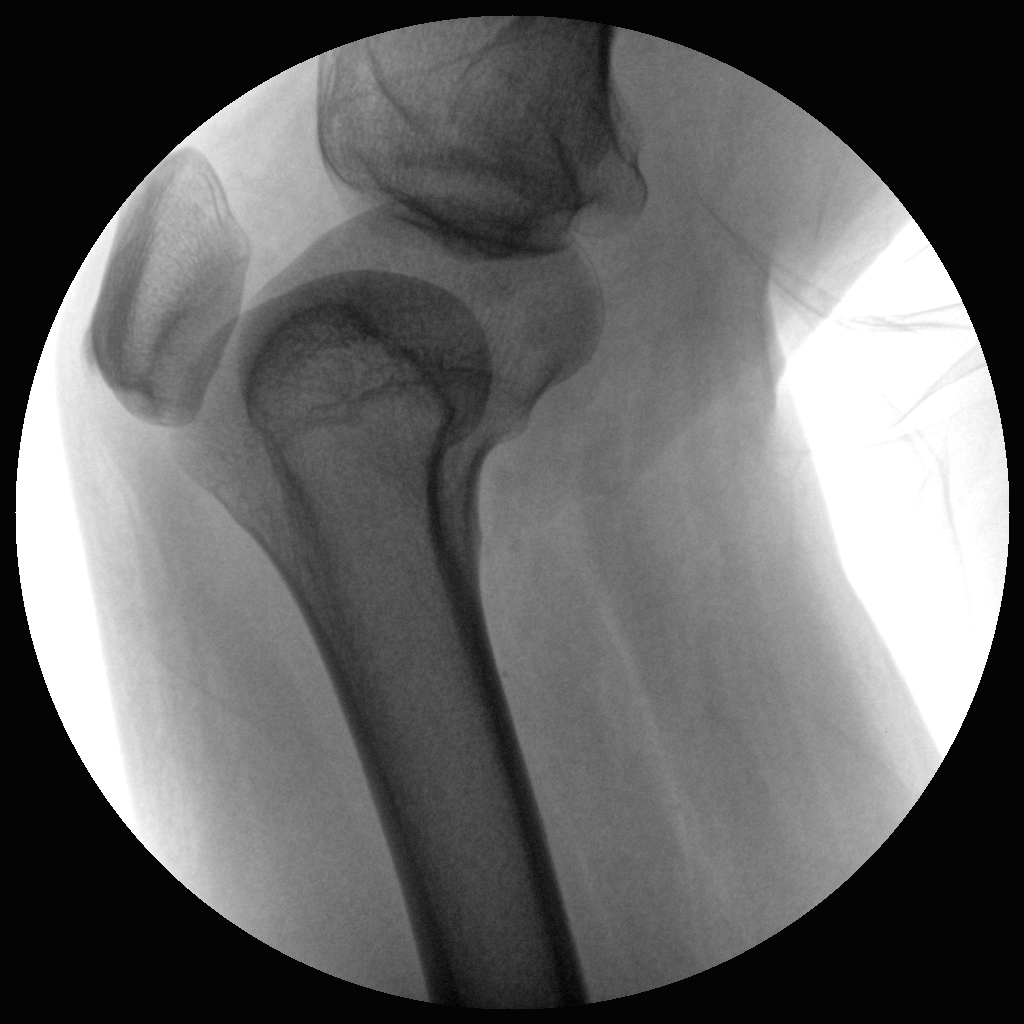

●全數(shù)字化百萬(wàn)像素影像系統(tǒng),圖像清晰

●靈活的C臂機(jī)架設(shè)計(jì),滿足臨床大范圍運(yùn)動(dòng)